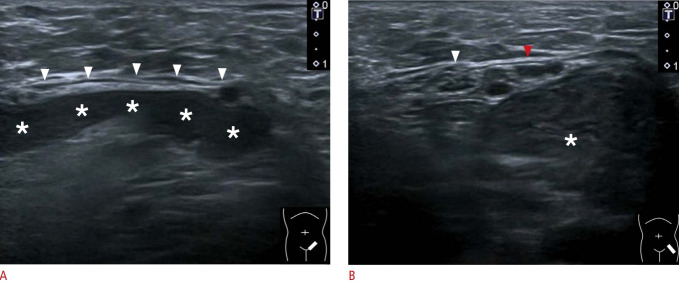

Your physician has diagnosed a hernia of sorts and there are several types and if its an inguinal hernia the next step in the journey will usually be an inguinal ultrasound. Move those underpants down, let the gel flow and the wand does its magic. No preparation No pain. No fuss. No loss of dignity. Thirty minutes you are done. You are rolling closer to your destiny.

An ultrasound report will be sent to the requesting physician and most likely you’ll be contacted by that physician’s office for a follow up appointment welcoming you to the hernia club.